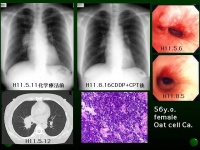

肺部良性肿瘤